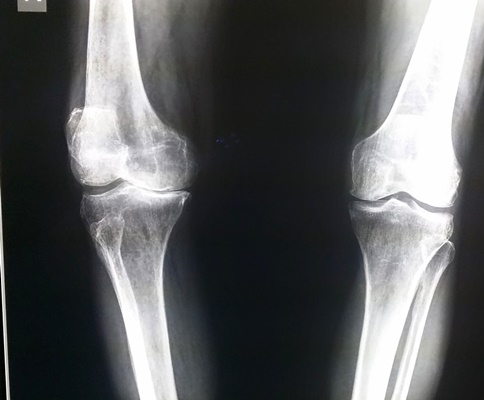

ในวันนี้ขอยกตัวอย่างผู้ป่วยโรคข้อเข่าเสื่อมทั้ง 2 ข้าง ที่ทำให้ผู้ป่วยมีอาการปวดข้อเข่า เดินลำบาก ข้อเข่าผิดรูป เดินเซและหกล้มได้ง่าย ซึ่งทำให้ผู้ป่วยใช้ชีวิตอย่างลำบากเป็นระยะเวลานานถึง 2 ปี ผู้ป่วยมีอาชีพรับราชการตำรวจ ทนทุกข์ทรมานจากอาการปวดเข่ามานาน ผู้ป่วยให้ประวัติว่า “เคยเจ็บเข่าจากอุบัติเหตุเล่นฟุตบอล จากนั้นก็เจ็บเข่าเป็นๆ หายๆ เรื่อยมา ในระยะสองปีมานี้อาการปวดเพิ่มขึ้นมากเรื่อยๆ คนรอบข้างเริ่มทัก โดยเฉพาะคุณแม่บอกว่าเดินไม่สวย เดินแปลกๆ เดินขาไม่ตรง เราก็ไม่ค่อยใส่ใจเท่าไหร่ จนมีอาการเจ็บมากจนทนไม่ไหว มาพบแพทย์ที่โรงพยาบาล แพทย์ได้ส่งตรวจทำการเอกซเรย์ เห็นได้ชัดเจนว่ากระดูกเข่าของเราชิดเข้าด้านในท่ายืนตรง แพทย์ได้แนะนำให้รักษาโดยการผ่าตัด ตอนแรกรู้สึกกังวล แต่เห็นกระดูกเข่าของตนเองจากภาพถ่ายรังสีแล้วก็คิดว่าถ้าปล่อยทิ้งไว้เข่าก็จะต้องชิดเข้ามากเรื่อยๆ ยังไงก็ต้องผ่าอยู่ดี และคิดว่าการเข้ารับการผ่าครั้งนี้ต้องเจ็บ ต้องปวดและใช้เวลาพักฟื้นนานแน่ๆ มีความกังวลว่ากระบวนการรักษาการผ่าตัดมันเป็นอย่างไร แพทย์จะทำอะไรกับเราบ้าง แต่หลังจากการได้คุยและได้รับคำแนะนำจากแพทย์ที่จะทำการผ่าตัด พร้อมกับเข้าไปศึกษาถึงวิธีการรักษา การปฏิบัติตัวและตัวอย่างประวัติการรักษาจากผู้ป่วยที่เคยรับการผ่าตัดรักษาเปลี่ยนข้อเข่าเทียมแล้ว ได้คลายความกังวลลงมาบ้าง หลังจากรับการรักษาด้วยการผ่าตัดเปลี่ยนข้อเข่าเทียมแล้วไม่ได้เจ็บปวดอย่างที่คิดไว้ สองวันแรกหลังผ่าตัดไม่ปวดเลย และเริ่มไปทำกายภาพ หัดเดินด้วยไม้สี่ขา หัดเหยียดเข่า งอเข่า ประมาณวันที่สี่เริ่มมีอาการระบม ปวด แพทย์ได้ให้ยาแก้ปวด อาการปวดทุเลาลงไป ทำกายภาพต่อได้สบาย มาตอนนี้หลังผ่าตัดประมาณยี่สิบวัน รู้สึกดีมาก แผลแห้งดี งอเหยียดเข่าได้เต็มที่ ยืนขาตรง เดินตรง เหมือนกับได้ชีวิตใหม่ขึ้นมาอีกครั้ง” สำหรับผู้ป่วยรายนี้ เนื่องจากเข่าของผู้ป่วยมีอาการผิดรูปทั้ง 2 ข้าง ทำให้ไม่สามารถเดินได้เป็นปกติ หลังจากที่ได้พูดคุยและอธิบายถึงข้อดีและความเสี่ยงจากการผ่าตัด เช่น โอกาสของการติดเชื้อ การเกิดลิ่มเลือดอุดกั้นในเส้นเลือดดำ การควบคุมอาการปวดหลังการผ่าตัด ก็ได้พิจารณารักษาด้วยการผ่าตัดเปลี่ยนข้อเข่าเทียมพร้อมกันทั้ง 2 ข้างให้กับผู้ป่วย หลังการผ่าตัดได้มีการให้ยาระงับปวดด้วยการวางสายเพื่อให้ยาลดอาการปวดที่โพรงประสาทในส่วนกระดูกสันหลัง ซึ่งผลการผ่าตัดทุกอย่างเป็นไปตามเป้าหมายที่วางไว้ คือ ลดอาการปวดข้อเข่าให้กับผู้ป่วย แก้ไขความผิดรูปของข้อเข่าทั้ง 2 ข้าง ทำให้ผู้ป่วยสามารถกลับมาเดินได้อย่างปกติ ทำให้ผู้ป่วยสามารถกลับไปใช้ชีวิตในสังคมได้อย่างมีความสุข ทำให้คุณภาพชีวิตของผู้ป่วยดีขึ้นเป็นอย่างมาก